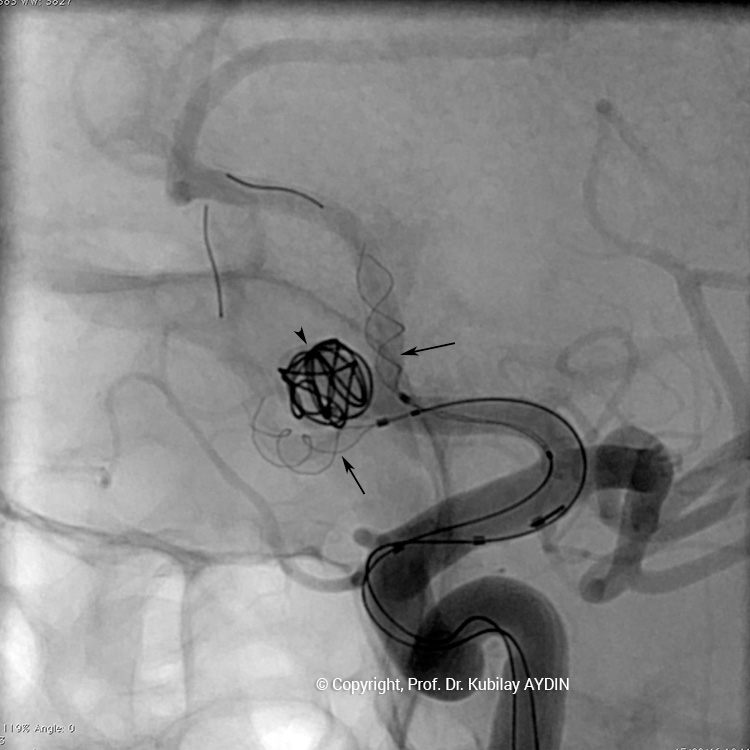

Geniş boyunlu anevrizmaların stent kullanılarak koillerle kapatılması işlemine “stent-yardımlı koilleme” adını veriyoruz. Bu işlemin ilk aşamasında anevrizmanın boynunu örtecek şekilde damar içine bir metal kafes (stent) yerleştirilerek, bir sonraki aşamada anevrizma kesesi içine konulan koillerin damar içine sarkması önlenir. Yani, burada stentin görevi, anevrizma içine doldurduğumuz koil adı verilen tellerin, damar içine sarkmasını önlemektir. Stent-yardımlı koilleme, geniş boyunlu anevrizmaların kapalı yöntemle tedavisinde tercih edilen bir yöntemdir.

Stent yardımlı koilleme tekniği ile anevrizma tedavisinde, anevrizmanın yerleştiği atardamar içerisine stent açılması için bir kateter yerleştirilir. Eş zamanlı olarak, anevrizma kesesi içerisine koilleme amaçlı farklı bir kateter yerleştilir. Damar içerisine bir stent açıldıktan sonra, anevrizma içerisideki kateterden gönderilen platinden yapılmış çok yumuşak yapıda koillerle anevrizma kesesi doldurulur. Stent, anevrizma içeriside bırakılan koillerin damar içine sarkmasına engel olur. Koilleme işlemine, anevrizma koillerle tamamen doldurulana ve anevrizma içine kan girmeyene kadar devam edilir.